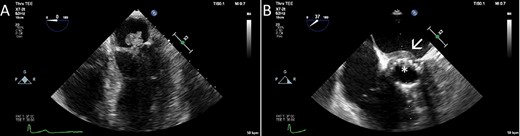

Gross images of the TAVI prosthesis showing vegetations in the stent ((A), (B)). The biological mitral (C) and aortic valve (D) prostheses were attached to a bovine pericardial patch, which was used to reconstruct the intervalvular fibrous body.

A full-median sternotomy was performed, and the heart was accessed after opening of the pericardial sac. After bicaval and aortic arch cannulation, the patient was put on cardio-pulmonary bypass and antegrade cardioplegia was delivered to induce asystole. A combination of antegrade and retrograde cardioplegia was iterated every 20 min during the procedure. The ascending aorta was incised above the TAVR prosthesis (Fig. 2A), on which small vegetations were found on the stent as well as on the leaflets (Fig. 2B). The TAVR prosthesis was removed and after removal of the native aortic valve, an abscess was found at the level of the commissure between the left- and non-coronary cusps. The aortotomy was therefore extended toward this area for better exposure, and the abscess had almost penetrated into the left atrium. The superior vena cava was opened above the sinus node to allow a better exposure to the left atrium. The left atrium was subsequently opened in the roof and the incision was connected to the aortotomy and further down to the anterior mitral leaflet which was excised. Pledgeted sutures were placed in the posterior mitral anulus and sutured to the posterior two-thirds of a 27 mm Perimount Magna, while the anterior one-third of the mitral valve prosthesis was attached to a bovine pericardial patch (Fig. 2C). A 21 mm Perimount Magna aortic valve prosthesis was then attached to the aortic anulus and the rest of the bovine pericardial patch with pledgeted sutures (Fig. 2D). The left atriotomy was closed using one side of the pericardial patch, and the other side of the pericardial patch was sutured to close the aortic root before continuing with the closure of the aortotomy. Perioperative TEE showed well-functioning biological prosthesis in both mitral and aortic positions without signs of paravalvular leak, and there was no flow across the bovine pericardial patch. The weaning from cardio-pulmonary bypass was relatively uncomplicated although the patient developed a third-degree atrioventricular block without junctional escape rhythm. Epicardial pacemaker electrodes were sutured to the right atrium and right ventricle and tunneled to the left infraclavicular fossa.